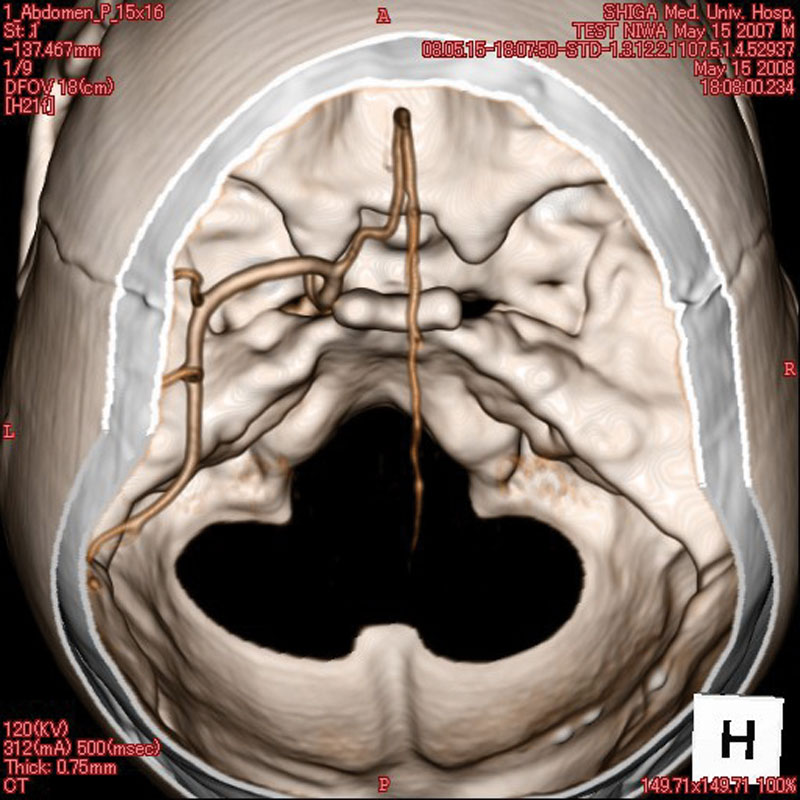

- Dieses Modell besteht aus einem synthetischen Schädel, welcher in einen Kunststoffkopf eingegossen ist.

- In der linken Schädelhälfte sind die vordere und mittlere Hirnarterie nachgebildet und mit Kontrastmittel gefüllt.

- Der Durchmesser der simulierten Arterien reicht von 0,5 mm bis 4 mm.